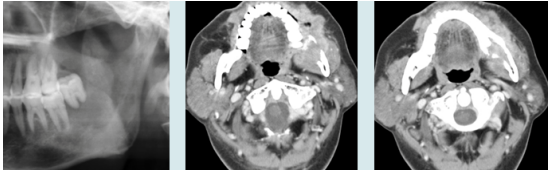

74.下圖三張影像所呈現的病灶區,其臨床診斷最可能為下列何者?

(A)纖維性發育不良(fibrous dysplasia) (B)鱗狀細胞癌(squamous cell carcinoma) (C)纖維瘤(fibroma) (D)造釉細胞瘤(ameloblastoma)